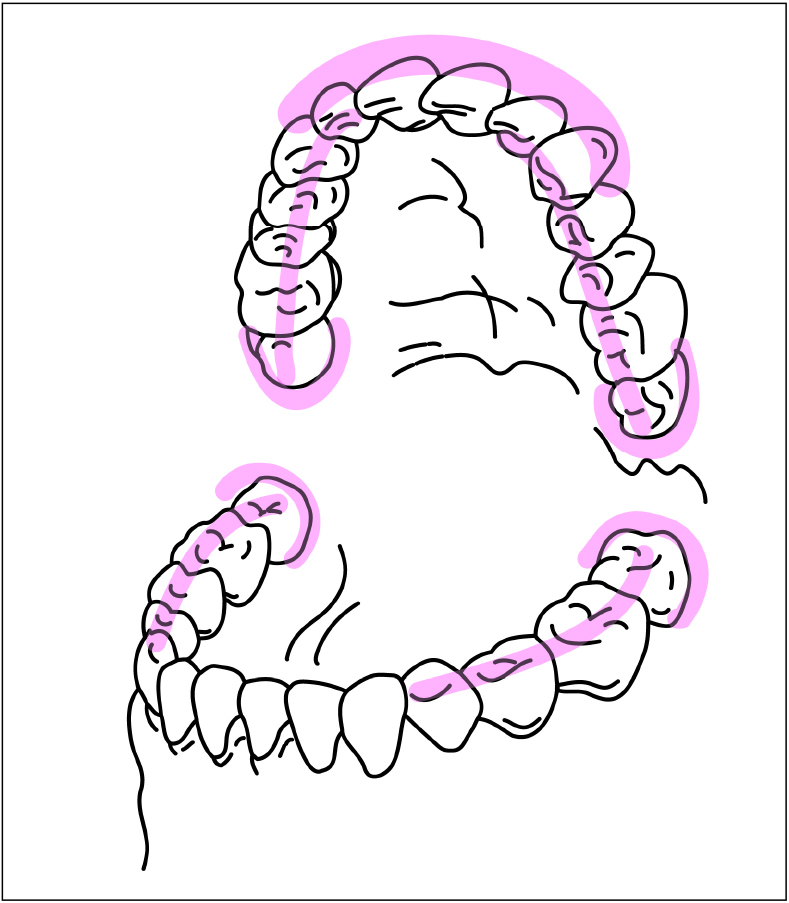

最後に虫歯になりやすい歯について見ていきましょう。

歯には虫歯になりやすい部位があります。どこが虫歯になりやすいのでしょうか?

それは口腔内の唾液の流れにも大きく関係しているのです。口腔内の唾液の流れは河の本流と支流のようになっています。そのため、大量の刺激唾液に洗われる部位もあれば、少量の安定唾液に常に洗われる部位、また十分な舌の運動なしには唾液の恩恵をほとんど受けることのできない部位もあります。

虫歯になりやすい部位

図は、口腔内で唾液の影響を受けることが少なく、したがって虫歯になりやすい部位を示したものです。

このような部位をより注意してブラッシングすることで虫歯を防ぐことができます。

また、上の奥歯と上の前歯の頬側に虫歯がある、治療回数が多いという場合には、その人の虫歯リスクは高いことが予想されます。